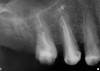

Figure 4  Occlusal view of the healed bony ridge, taken at the time of implant placement.

Figure 4

The grafted sites were followed clinically and radiographically throughout the healing period. Healing of the residual crestal defects (if present) also was followed. At approximately 6 months, the patients returned for graft analysis and placement of implants. Clinical photographs and radiographs were taken preoperatively. After administration of local anesthesia and minimal flap elevation, measurements of alveolar ridge width were repeated to compare with the preoperative alveolar dimensions (Figure 4). The coronal portions of the regenerated sites were evaluated for the presence of residual graft material. Preparation of the osteotomies was initiated with a bone trephine to sample the coronal 5 mm to 7 mm of socket healing (Figure 5). The placement of appropriately sized dental implants was performed according to the manufacturer’s recommendations, and the flaps were sutured to facilitate both soft- and hard-tissue healing.